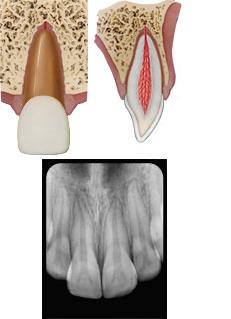

Root fracture

Definition: a dentin and cementum fracture involving the pulp.

Diagnosis: Clinical findings reveal a mobile coronal fragment attached to the gingiva that may be displaced. Radiographic findings may reveal 1 or more radiolucent lines that separate the tooth fragments in horizontal fractures. Multiple radiographic exposures at different angulations may be required for diagnosis. A root fracture in a primary tooth may be obscured by a succedaneous tooth.